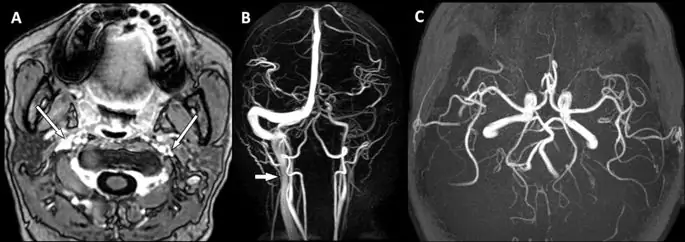

Мы провели 1.5Т МРТ (Excite II; GE Medical Systems, Милуоки, Висконсин) для всех участников. Последовательности визуализации были осевыми T1-взвешенными и контрастными осевыми T1-взвешенными изображениями. Усиленные контрастом осевые T1-взвешенные изображения простирались от черепа до уровня грудного входа у пациентов с ТМБ (те же последовательности контрольных лиц не охватывали нижний уровень IJV и грудной вход) со следующими параметрами: время повторения (TR) = 8, 6 миллисекунд, время эха (TE) = 2, 5 миллисекунды, время инверсии (TI) = 400 миллисекунд, угол переворачивания = 15 °, толщина среза = 1, 5 мм, поле зрения (FOV) = 24 см, матрица = 320 × 256, Трехмерную МР-ангиографию во время полета (MRA) применяли для исключения пациентов со стенозом сонной артерии и другими очевидными артериальными источниками, которые могут приводить к появлению симптомов (рисунок 1), с параметрами: время повторения (TR) = 30 миллисекунд время эха (TE) = 6, 9 миллисекунды, угол переворачивания = 20 °, толщина среза = 1, 8 мм.

фигура 1

МРТ исследования у пациентов с ТМБ со стенозами IJV. Это 46-летняя женщина с рецидивирующей и преходящей монокулярной слепотой над правым глазом. Усиленное по контрасту осевое T1-взвешенное изображение (A) показало двусторонние стенозы IJV (стрелки). (справа IJV: 1 класс; слева IJV: 3 класс). МР-ангиограмма (B) показала снижение венозного кровотока по левосторонним венозным путям и очаговое сужение по правостороннему IJV (стрелка), в то время как артериальная система была относительно нормальной, что также было показано на трехмерной МР-ангиограмме во время полета (C), Изображение в полном размере